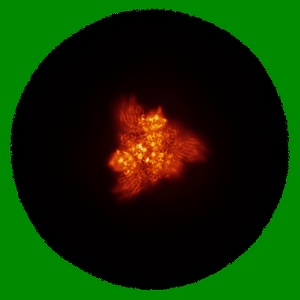

Cryo-EM structure of SARS-CoV-2 S-BQ.1 in complex with antibody O5C2

Single-particle3.6 Å

Sample: SARS-CoV-2 S-BQ.1 and antibody O5C2 complex

Functional and structural investigation of a broadly neutralizing SARS-CoV-2 antibody.